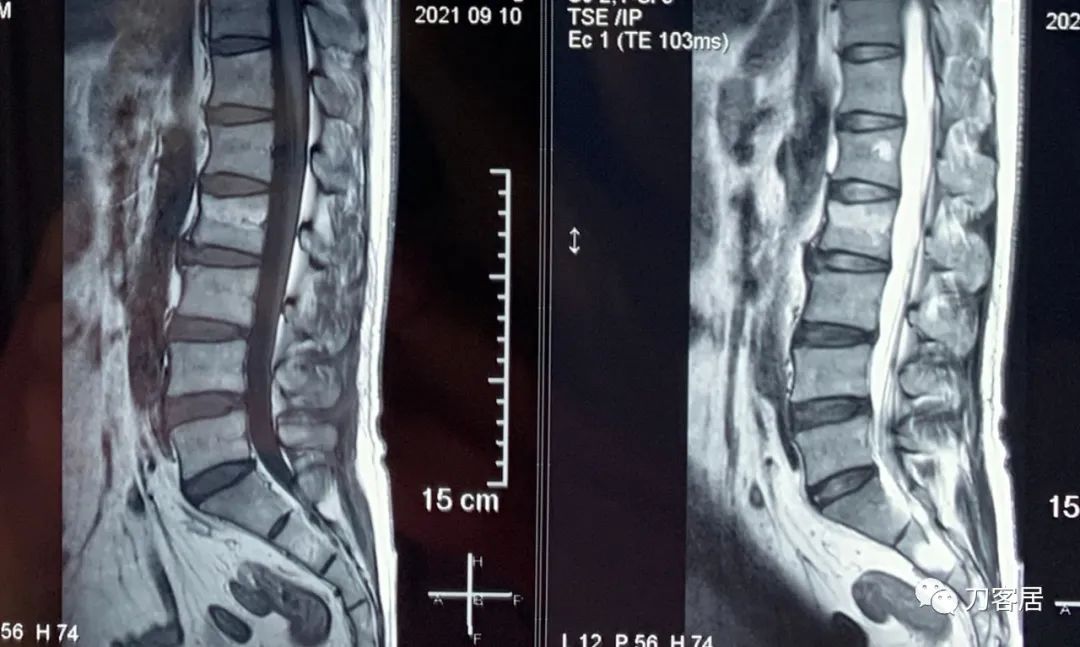

2021年9月1日在宁夏大学总医院做的腰椎MRI提示腰2椎体压缩骨折,不严重。

虽然该患者携带的磁共振片子上显示腰2椎体压缩骨折是新鲜骨折,但该片子是2021年9月1日的片子,已过1年5个月,骨折已是陈旧骨折,拍摄普通X线片证明腰2椎体压缩骨折较前无加重,因此无需再做腰椎MRI片子,节省患者的费用。